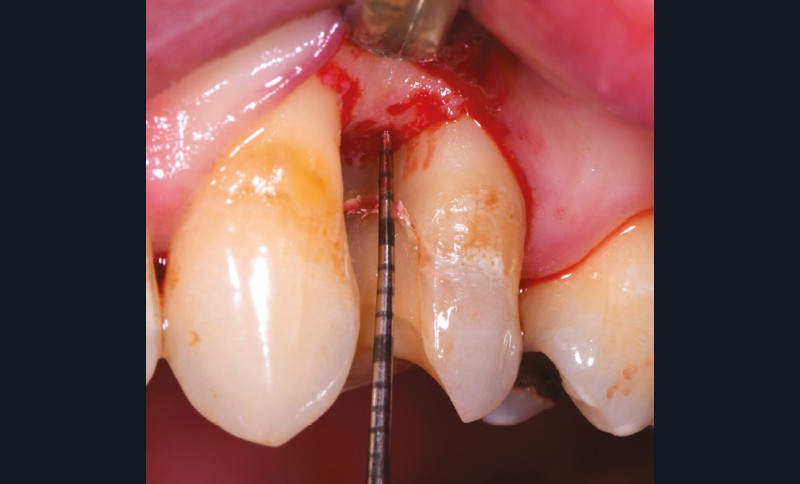

Lorsque l’indication est posée, le choix de la technique chirurgicale doit répondre à des contraintes anatomiques et esthétiques qui seront détaillées afin de choisir l’abord chirurgical adapté et ainsi maximiser les résultats (fig. 7 à 9).

Ces deux techniques sont complémentaires et ont prouvé leur fiabilité [11]. Il serait nécessaire de réaliser des études cliniques prospectives contrôlées et randomisées pour évaluer l’impact de la remontée de marge sur la longévité des restaurations. En l’état actuel des connaissances, lorsque le protocole de collage est parfaitement mené avec des matériaux et un polissage de qualité, et lorsque l’indication est la bonne, la DME apparaît comme une approche conservatrice intéressante.

Dans la même idée de complémentarité entre manipulation parodontale et remontée de marge, la solution dans certains cas complexes ne serait-elle pas de combiner un lambeau à la pose du champ opératoire pour faciliter la remontée de marge et accéder aux limites ?